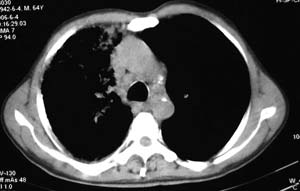

右侧胸廓略小于左侧,右肺上叶大片实变影,近肺门处密度较高,内见支气管气相,周围较淡,呈网格状,余肺野清晰,纵隔内见肿大淋巴结,右侧胸腔少量积液。临床 咳血,咳痰 发热 , 血象1.2万。

考虑大叶性肺炎。

鉴别,细支气管肺泡癌,弥漫性可有病变侵犯一个肺叶,呈炎性实变,密度偏高,可见支气管气相、蜂窝状气腔,与本例影像上不易鉴别,但临床多为咳嗽、咳白色泡沫痰,感染症状轻。

影像表现:肺窗示右肺上中叶均可见小片、条索状、小结状密度增高影,可见支气管充气相,小叶间隔增厚,支气管通畅,余肺未见明显异常。纵隔窗示4r可见小淋巴结融合,无明显肿大,右侧示少量胸腔积液。

男 64  咳血,咳痰 发热 3天 血象1.2万;右肺上叶满布片絮状致密灶,其内见含气支气管影,右主支气管狭窄,纵隔内见肿大淋巴结。考虑右肺中央型肺癌伴阻塞性肺炎,建议支气管镜检查。

右侧胸阔塌陷,纵隔右移。右上肺大片状高密度影,沿支气管血管束走行,内见点状钙化;支气管充气征阳性,支气管呈柱状扩张;胸膜下小叶间隔增厚;右侧后胸壁内侧见带状水样密度影;纵隔淋巴结增大。

考虑:①右上叶陈旧性结核合并感染可能大。②右侧少量胸水。